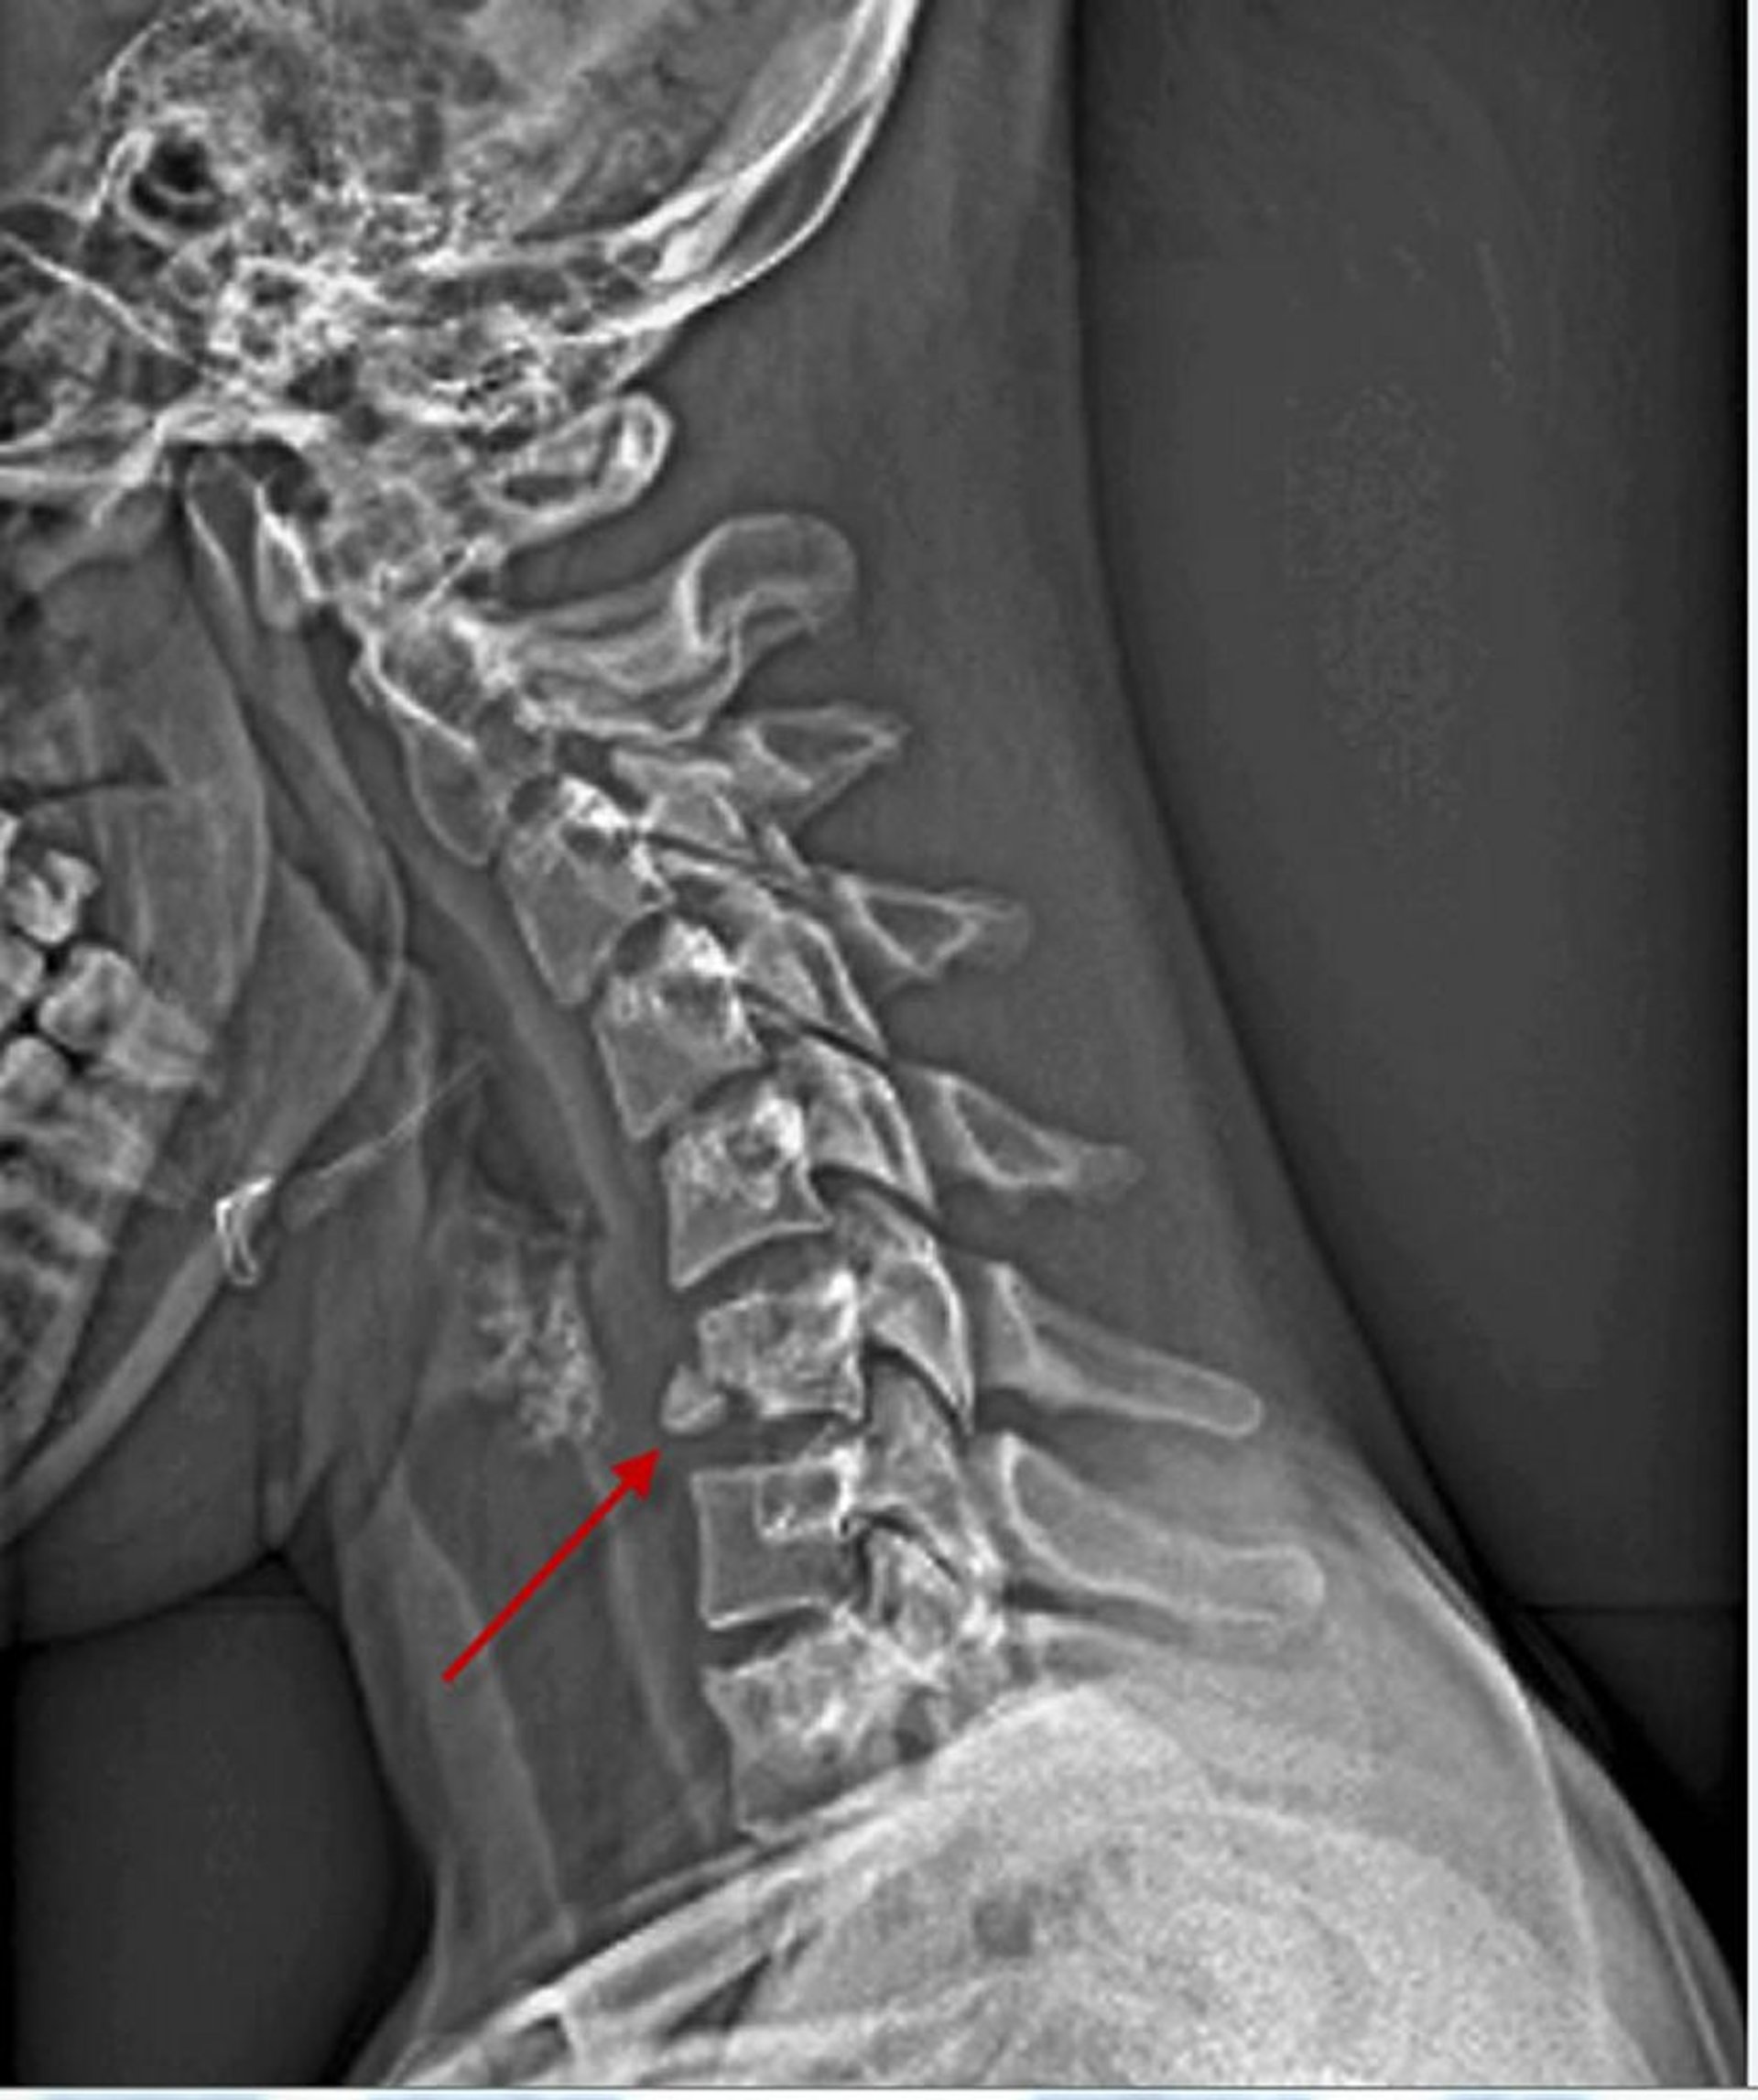

Cervical Vertebral Body Fracture

This lateral view of the cervical spine shows a fracture of the inferior, anterior aspect of the 6th vertebral body (arrow).